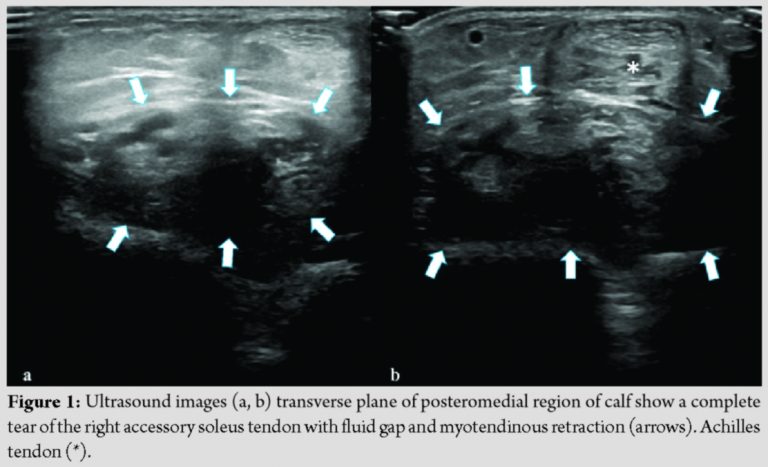

US evaluation of the calf and ankle was subsequently performed showing normal findings of the Achilles tendon, soleus muscle, plantaris tendon, and both medial and lateral heads of the gastrocnemius; color Doppler US excluded deep vein thrombosis. However, examination of the posteromedial region showed fluid gap with a myotendinous retraction suspicious for an accessory soleus tear muscles with a complete tear of tendon with a myotendinous retraction (Fig. 1). MRI confirmed the diagnosis and demonstrated complete tear of the right accessory soleus tendon with surrounding edema, myotendinous retraction measuring 26 mm, fluid gap into the Achilles fat pad (Kager’s triangle), and minimal joint effusion in the tibiotarsal joint and in the subtalar joint (Fig. 2). No other abnormalities were detected on MRI.